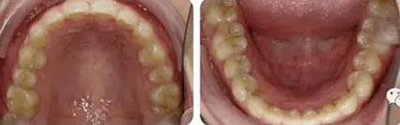

上下牙列輕度擁擠,牙弓偏尖圓形;前牙深覆合深覆蓋;雙側(cè)磨牙尖牙偏遠(yuǎn)中關(guān)系。